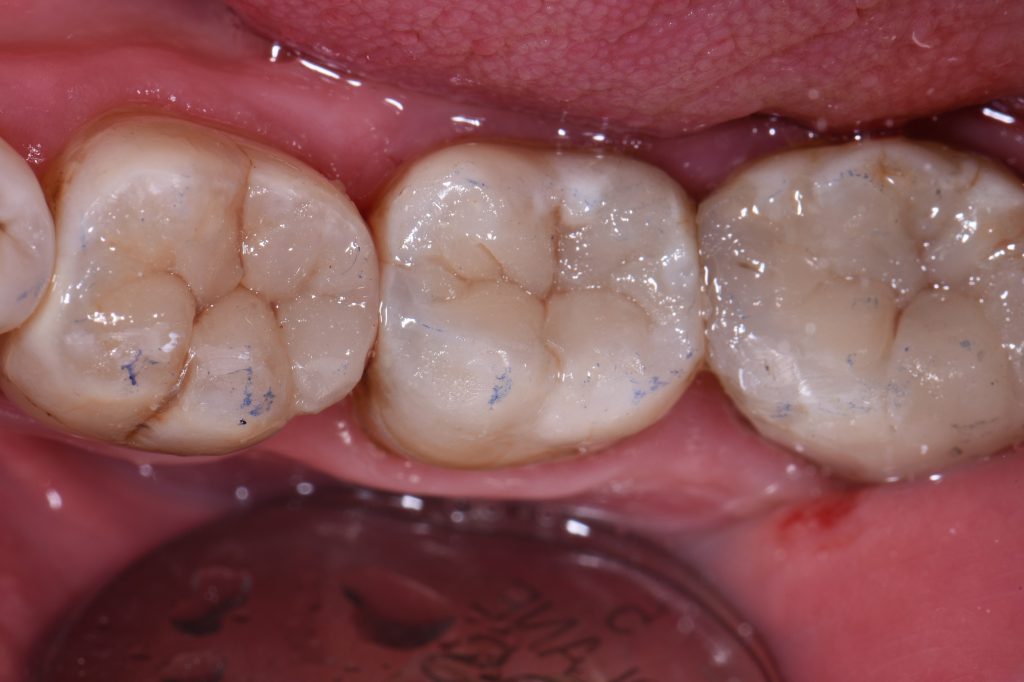

This patient presented with generalised failure of his old composite and amalgam restorations, tooth 47 specifically exhibiting a stained hairline fracture on the OL (distal aspect) with recurrent caries under the amalgam as a result.  A single shade of the A2.5 Venus Pearl shade from Kulzer was applied in conjunction with the Garrison Compositight 3D Fusion system to restore this quadrant with a naturomimetic focus.  iBond Universal was used as the bonding agent with a selective etching approach (this is predictable as it contains 10-MDP, the acidic monomer with calcium salt layering resulting in a near-invincible hybrid layer)